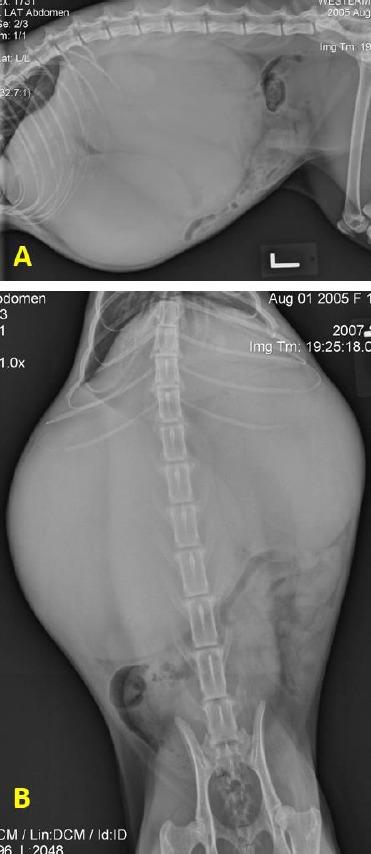

A 2 year old, spayed female African serval was evaluated for a history of abdominal distention. Physical examination findings were consistent with cranial abdominal masses and anemia. Abdominal imaging revealed soft tissue opacity masses in the cranial abdomen and hypoechoic cysts arising from the liver parenchyma. Conservative management failed to improve clinical signs, and a midline exploratory laparotomy was performed. Three large hemorrhagic cysts were visualized occupying a significant amount of the liver parenchyma. The cysts were drained, omentalized and partially closed with a surgical stapler and suture. Histopatological evaluation of the resected tissue was consistent with a chronic hepatic hematoma. The patient recovered well and was discharged 3 days postoperatively. Two years later, the patient was readmitted with the same clinical signs and large multiple hepatic cysts involving most of the liver lobes. These were surgically omentalized similarly to the previous surgery and the patient recovered well postoperatively. Two years later, return to normal life and no recurrence of the cysts was reported.

一只2岁已绝育的雌性非洲薮猫因腹胀病史接受评估。体格检查结果与上腹部肿块和贫血相符。腹部影像学检查显示上腹部有软组织密度肿块,肝实质内有低回声囊肿。保守治疗未能改善临床症状,遂进行了中线剖腹探查术。可见三个大的出血性囊肿占据了大量肝实质。囊肿被引流、网膜化,并用外科吻合器和缝线部分封闭。切除组织的组织病理学评估结果与慢性肝血肿一致。患者恢复良好,术后3天出院。两年后,患者因相同临床症状再次入院,发现肝脏多个大叶有大量囊肿。这些囊肿同样通过手术进行网膜化处理,患者术后恢复良好。两年后,患者恢复正常生活,未报告囊肿复发。